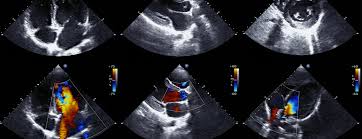

Echocardiogram

An echocardiogram is an ultrasound scan that captures real-time images of the heart, showing how it beats and pumps blood. These visuals help physicians identify potential issues such as irregular heart rhythms or structural abnormalities. The procedure is a standard diagnostic tool in cardiology. Its utility lies in its ability to provide clear and immediate images of the heart’s chambers, valves, walls, and blood vessels, making it a helpful technique in understanding heart performance.